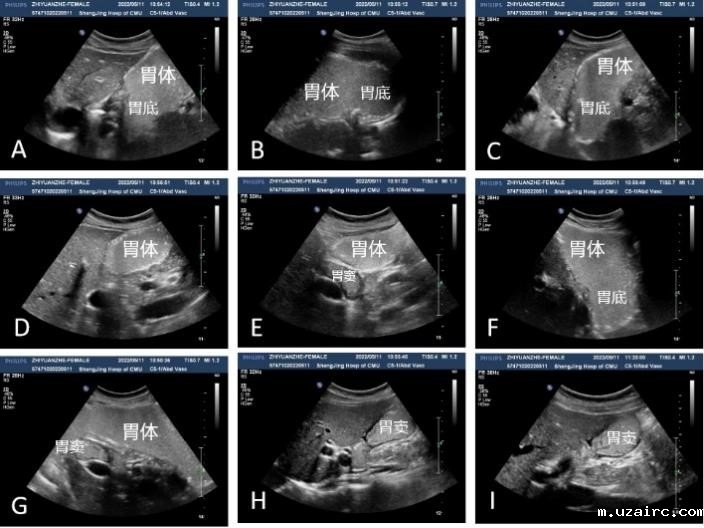

志愿者口服即用型造影剂后采用“胃超声五步九面”法检查,胃各部分的超声显像图

为了完成健康中国2030年“胃癌五年生存率提高到50%”的目标,急需建立适合中国国情的体检胃癌筛查体系。相关权威指南和规范均明确指出:胃镜、钡餐、幽门杆菌检测、胶囊胃镜等均难以成为我国大规模体检胃癌筛查的首选方式。从体检人群接受度、中国人口多等国情考虑,胃超声将更具优势。

目前已经上市的胃超声造影剂的共同缺点:为含淀粉类产品,需90℃以上开水冲泡配制,服用体积大(约600ML)须长时间等待放凉后服用,难以适用于体检中心及医院大规模使用场景。该项目所研制的超声造影剂属于二类医疗器械,可以用各种温度水兑服,混合迅速、实现“即冲即饮”,将加快推动胃癌筛查行业的发展。